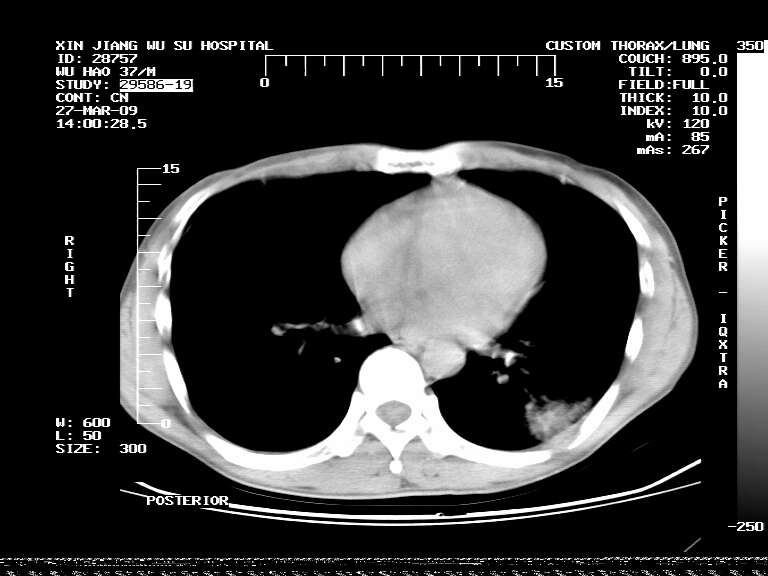

男,37岁,体检胸透发现阴影。

患者体检发现 无症状 左肺下叶占位,边缘模糊,可见血管聚束、分叶、胸膜牵拉,增强呈不均匀性强化。 首先考虑左肺下叶周围型肺癌,建议穿刺活检。

左肺下叶见一结节病变,边缘欠清不光滑,与胸膜粘连且胸膜局限性增厚,注药后呈环形强化,动脉期壁呈明显点环状强化,静脉期壁强化减低,中心密度低无强化,灶周无明显的卫星灶和水肿区(晕征)---考虑周围性肺癌,不除外感染性病变,建议穿刺活检。

左肺下叶软组织病灶,密度较高,内见点状钙化,其周围见子灶,邻近胸膜扁平样增厚.c+病灶强化明显,中心强化弱.诊断:左肺下叶结核瘤.

左肺下叶大片实变影,内靠胸膜见不规则更高密度结节灶,边缘强化,相邻胸膜增厚,胸膜下脂肪线存在。考虑炎症,结核可能。